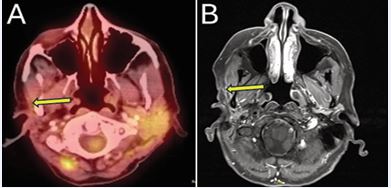

PET/CT obtained three months post-treatment showed reduction of the lesion to 7 mm and complete resolution of FDG uptake, consistent with complete response (Figure 7A).

https://www.jscimedcentral.com/public/assets/images/uploads/image-1766379384-1.JPG

Figure 7 (A) PET/CT three-months post-treatment demonstrating resolution of FDG uptake. (B) Contrast-enhanced neck MRI obtained the following year redemonstrating no evidence of disease.

She continued routine contrast-enhanced MRI surveillance annually thereafter, with all imaging throughout four years of follow-up showing no evidence of residual or recurrent disease (Figure 7B). By two years after treatment, she reported only mild focal tightness at the treated site consistent with low-grade fibrosis, which has remained stable over time.